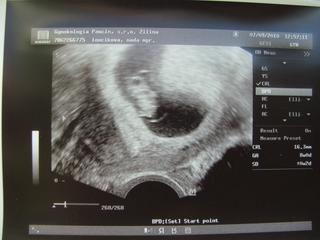

Tak dnes som bola prvýkrát u dr., malému bije srdiečko, všetko je v poriadku a vyfasovala som aj knižku 🙂 . Odbery zatiaľ žiadne, až o 4 týždne. Júúúj, tak sa teším 😵 😵 😵

ahojte kocky..tak dnes som videla srdiecko bit🙂))dostala som uz aj knizku a nakoniec mam termin 17.4 zatial...inac vsetko v poriadku a mam prist o mesiac..